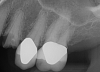

Fig 1. Preoperative surgery.

Figure 1

Fig 8. Preoperative periapical radiograph.

Figure 8